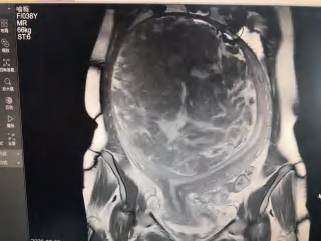

子宫肌瘤磁共振图